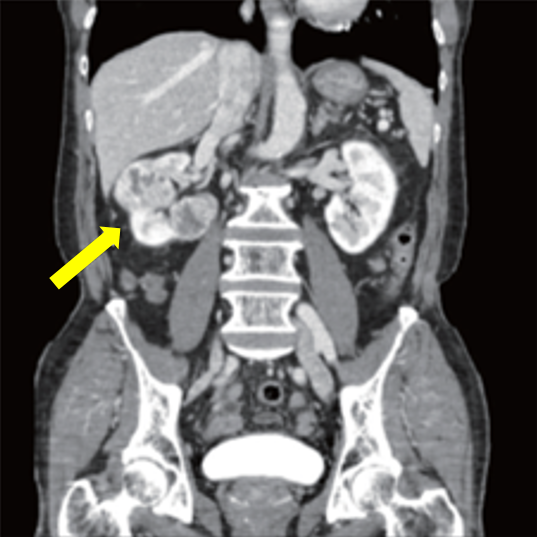

신장암은 초음파, CT, MRI 등 영상검사로 진단한다. 초음파검사로 옆구리 혹 유무를 확인하며, 혹이 확인된 경우 정확한 진단을 위해 복부CT검사를 진행한다. MRI 검사는 CT 외 추가감별진단에 도움이 되며, 특히 신세포암이 하대정맥(혈액을 심장의 우심방으로 운반하는 인체 내 가장 큰 정맥)을 침범하여 혈관 속 종양이 존재하는 경우 그 범위를 평가하는 데 사용된다.

신장암이 전이되어 간, 대장, 췌장 등 주변 장기로 침범한 경우에도 CT 검사로 진단이 가능하다. 뼈로 전이되는 경우에는 방사성동위원소를 이용한 뼈 스캔 검사를 시행한다.